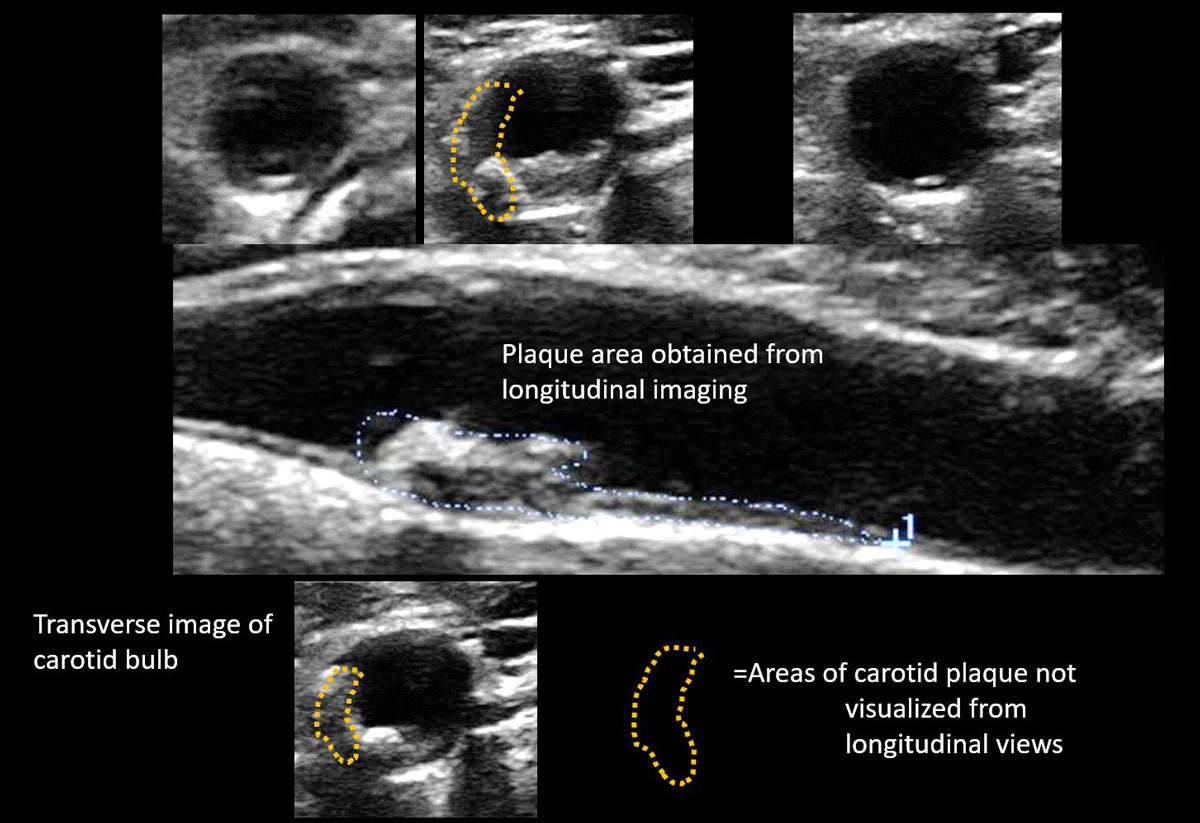

초음파를 통해 혈관 내막-중막 두께(IMT)를 측정함으로써 초기 단계의 동맥경화 여부를 파악할 수 있습니다. IMT가 정상 범위를 벗어나 두꺼워져 있다면 전신 동맥경화 위험이 높다고 판단합니다.